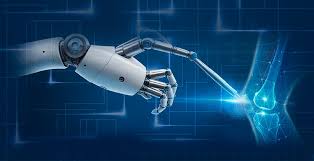

Introduction Robotic orthopedic surgery in Gariaband represents a major advancement in the treatment of complex bone and joint conditions. Many patients experience chronic pain, limited mobility, and reduced quality...

Introduction Robotic hip replacement in Gariaband offers an advanced solution for patients suffering from severe hip pain, stiffness, and reduced mobility. Many individuals find it difficult to perform daily...

Introduction Robotic joint replacement in Gariaband has transformed the way complex orthopedic conditions are treated. Patients suffering from chronic joint pain, stiffness, and reduced mobility often find it difficult...